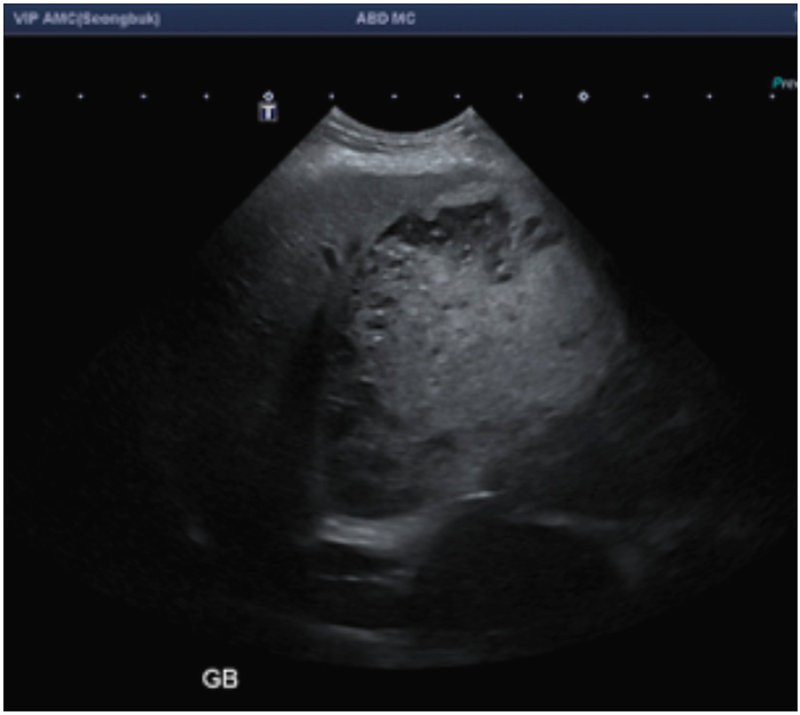

보호자분이 본원에 내원하기 직전 병원에서 검사했던 초음파 검사 사진을 봤을 때 굉장히 팽창되어 있다는 게 눈에 띄었습니다.

본원에서 다시 평가를 했을 때에도 담낭을 메우고 있는 물질의 양상은 Type 2에 해당하는 비교적 초기 상태이긴 하지만 담낭이 굉장히 팽만된 상태였고, 이런 흐름이 지속되어 간다면 주변으로 염증을 유발하여 간에도 더 큰 영향을 줄 수 있고 기력 저하, 식욕 부진의 증상이 나타날 수 있는 상태였습니다.

(내원 직전 병원에서 검사한 초음파 사진 ▲)

(본원에서 검사한 초음파 사진. 담낭 슬러지가 담낭 전체를 가득 메우고 있고, 변연부에 점액성 변화를 보이는 물질들이 생성되어 가는 중. 담낭점액종 Type 2. ▲)